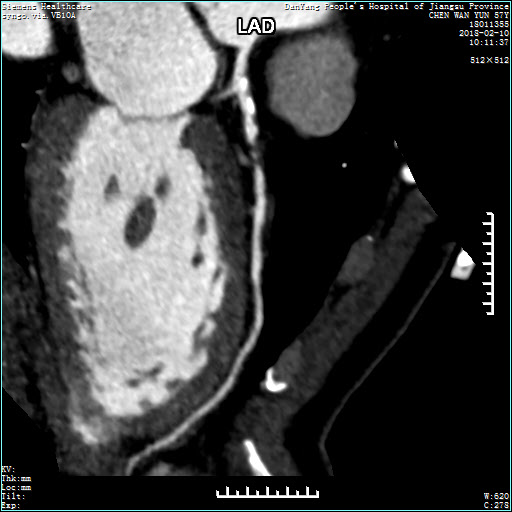

该设备为双球管双探测器系统CT,具有冠状动脉成像、脑动脉成像,血管曲面成像、高分辨率成像、多重三维成像等优势,可通过对人体进行多方位、多期相观察,获得不同部位的解剖数字图像,提供病灶的部位、结构、毗邻关系及生理病理等信息,以早期发现微小病变,定位准确、无创伤。

0.28秒心脏成像,尤其适用于房颤、早搏等心律不齐患者的检查,能够清晰的显示心脏冠状动脉,发现有无冠状动脉狭窄,评估狭窄的程度及原因,其冠状动脉扫描图像可和数字减影血管造影(DSA)媲美,却没有手术创伤,没有并发症,因此双源CT是诊断心脏冠状动脉狭窄、评价心脏支架置入及心脏冠脉搭桥术后病人情况的最佳选择